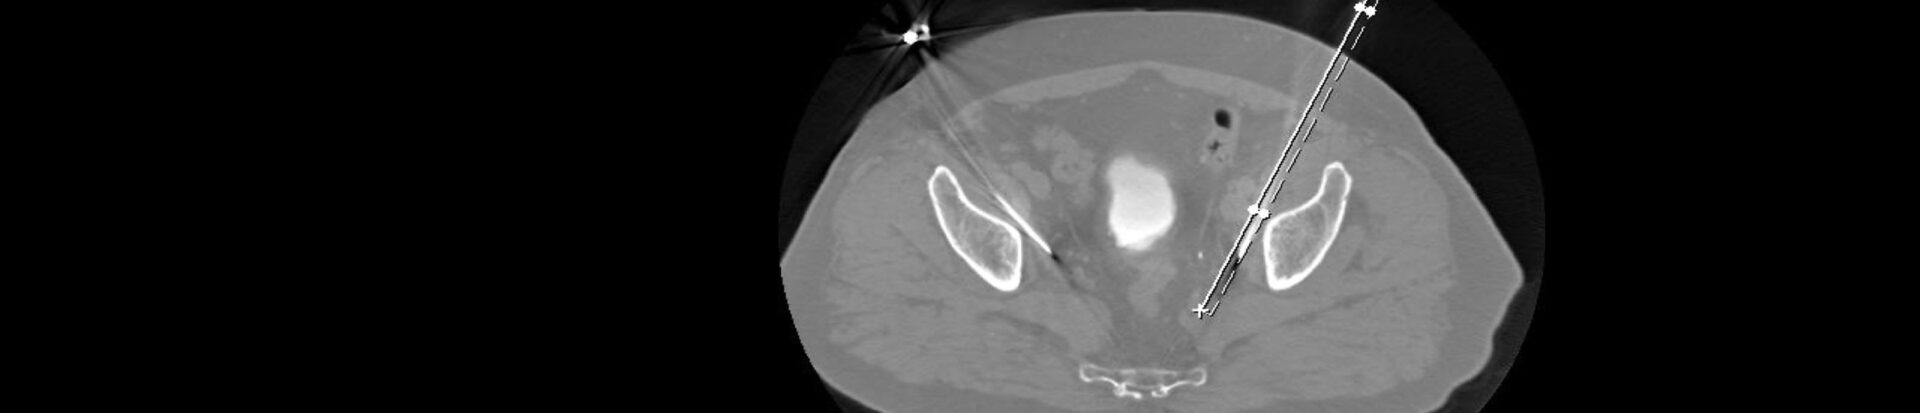

Zeigt die Bildgebung, daß nur eine oder wenige Lymphknotenmetastasen vorhanden sind, können diese, meist CT-gesteuert, durch das Einbringen von Instrumenten in über die Haut (perkutan) in den Lymphknoten zerstört – abladiert – werden.

Im VITUS Postata Center nutzen wir dazu ein Infrarot-Guidance System (Cascination, Schweiz), das es ermöglicht, in virtueller Realität den Patienten und seine Organe zu sehen und die für die Ablation benötigten Instrumente millimetergenau in der Metastase zu platzieren. Damit lassen sich auch schwierige Zugänge zu tief im Körper liegende Metastasen navigieren, ohne Gefäße, Nerven oder Organe zu verletzen.

Die Abbildungen zeigten CT und MRT-Scans eines Patienten mit Lymphknotenmetastasen bei einem Prostatakarzinom. Der Patient hatte sich einer Hormonentzugstherapie (ADT Androgen-Deprivations-Therapie) unterzogen, die nicht mehr wirkte. Der PSA-Spiegel war auf 8,65 ng/ml angestiegen. Die Lmyphknotenmetastasen (MRT-Bild rechts oben, Pfeile) sind tief im Becken im Bereich der großen Beckengefäße (Iliakalgefäße) und direkt neben den Ischiasnerven (Nervi ischiadici) lokalisiert. Das Bild rechts oben zeigt die Einbringung der Elektroden in die Lymphknoten im Computertomographen mit Hilfe des infrarotgesteuerten virtual Reality Systems Cascination. Das CT-Bild links unten zeigt die Elektroden in ihrem Verlauf von der Bauchwand bis in die metastasenbefallenen Lymphknoten. Das MRT-Bild rechts unter zeigt das Ergebnis fünf Monate später: Die Lymphknotenmetastasen sind vollständig verschwunden, der PSA-Spiegel sank auf 0,06 ng/ml ab.